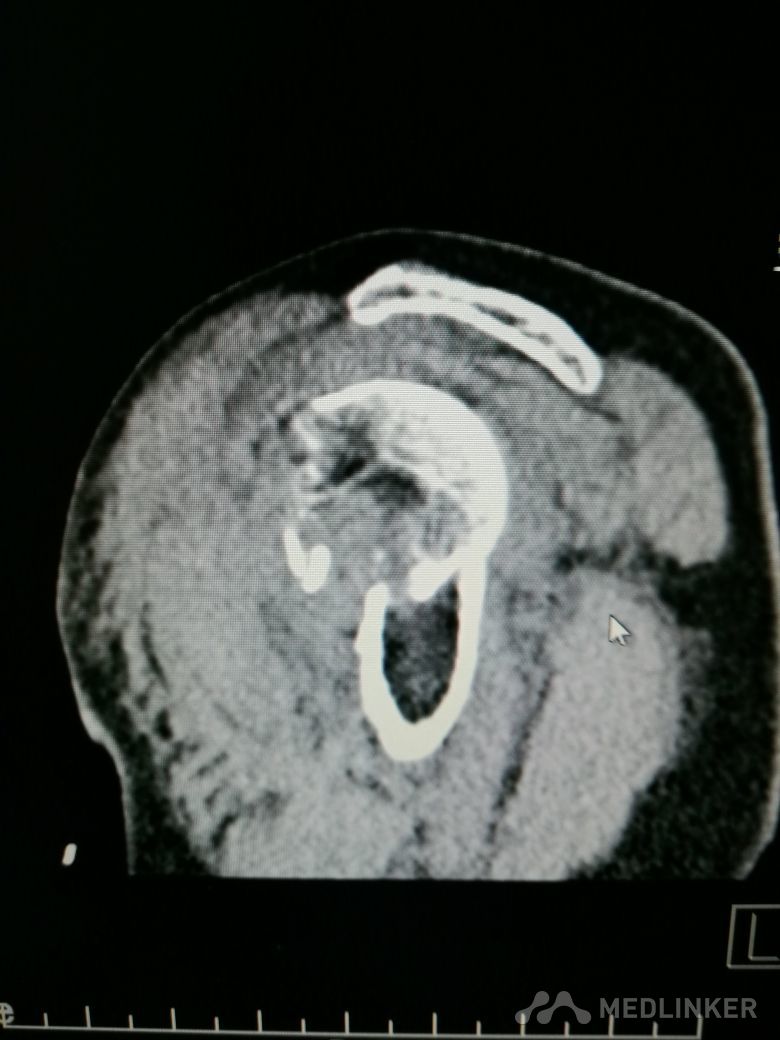

肱骨近端骨折 Neer IV型

患者,女性,55岁,因外伤致左肩疼痛六小时入院,既往无其他慢性病史

查体 右肩肿胀,畸形,活动受限,压痛,皮下淤血,右桡动脉搏动存在

完善相关检查,在腰麻下行右肱骨近端骨折切开复位内固定术

肱骨近端骨折占到肱骨骨折的45%,肱骨近端锁定钢板具有低切迹、高弹性、生物力学性能优良等特点,可以起到角度稳定控制旋转的作用。但是对于严重粉碎性肱骨近端骨折而言,单纯的肱骨近端锁定钢板不一定能够提供稳定的固定,手术之后仍有可能出现内翻塌陷、前后成角、螺钉切出、骨折畸形愈合、骨折不愈合等并发症。